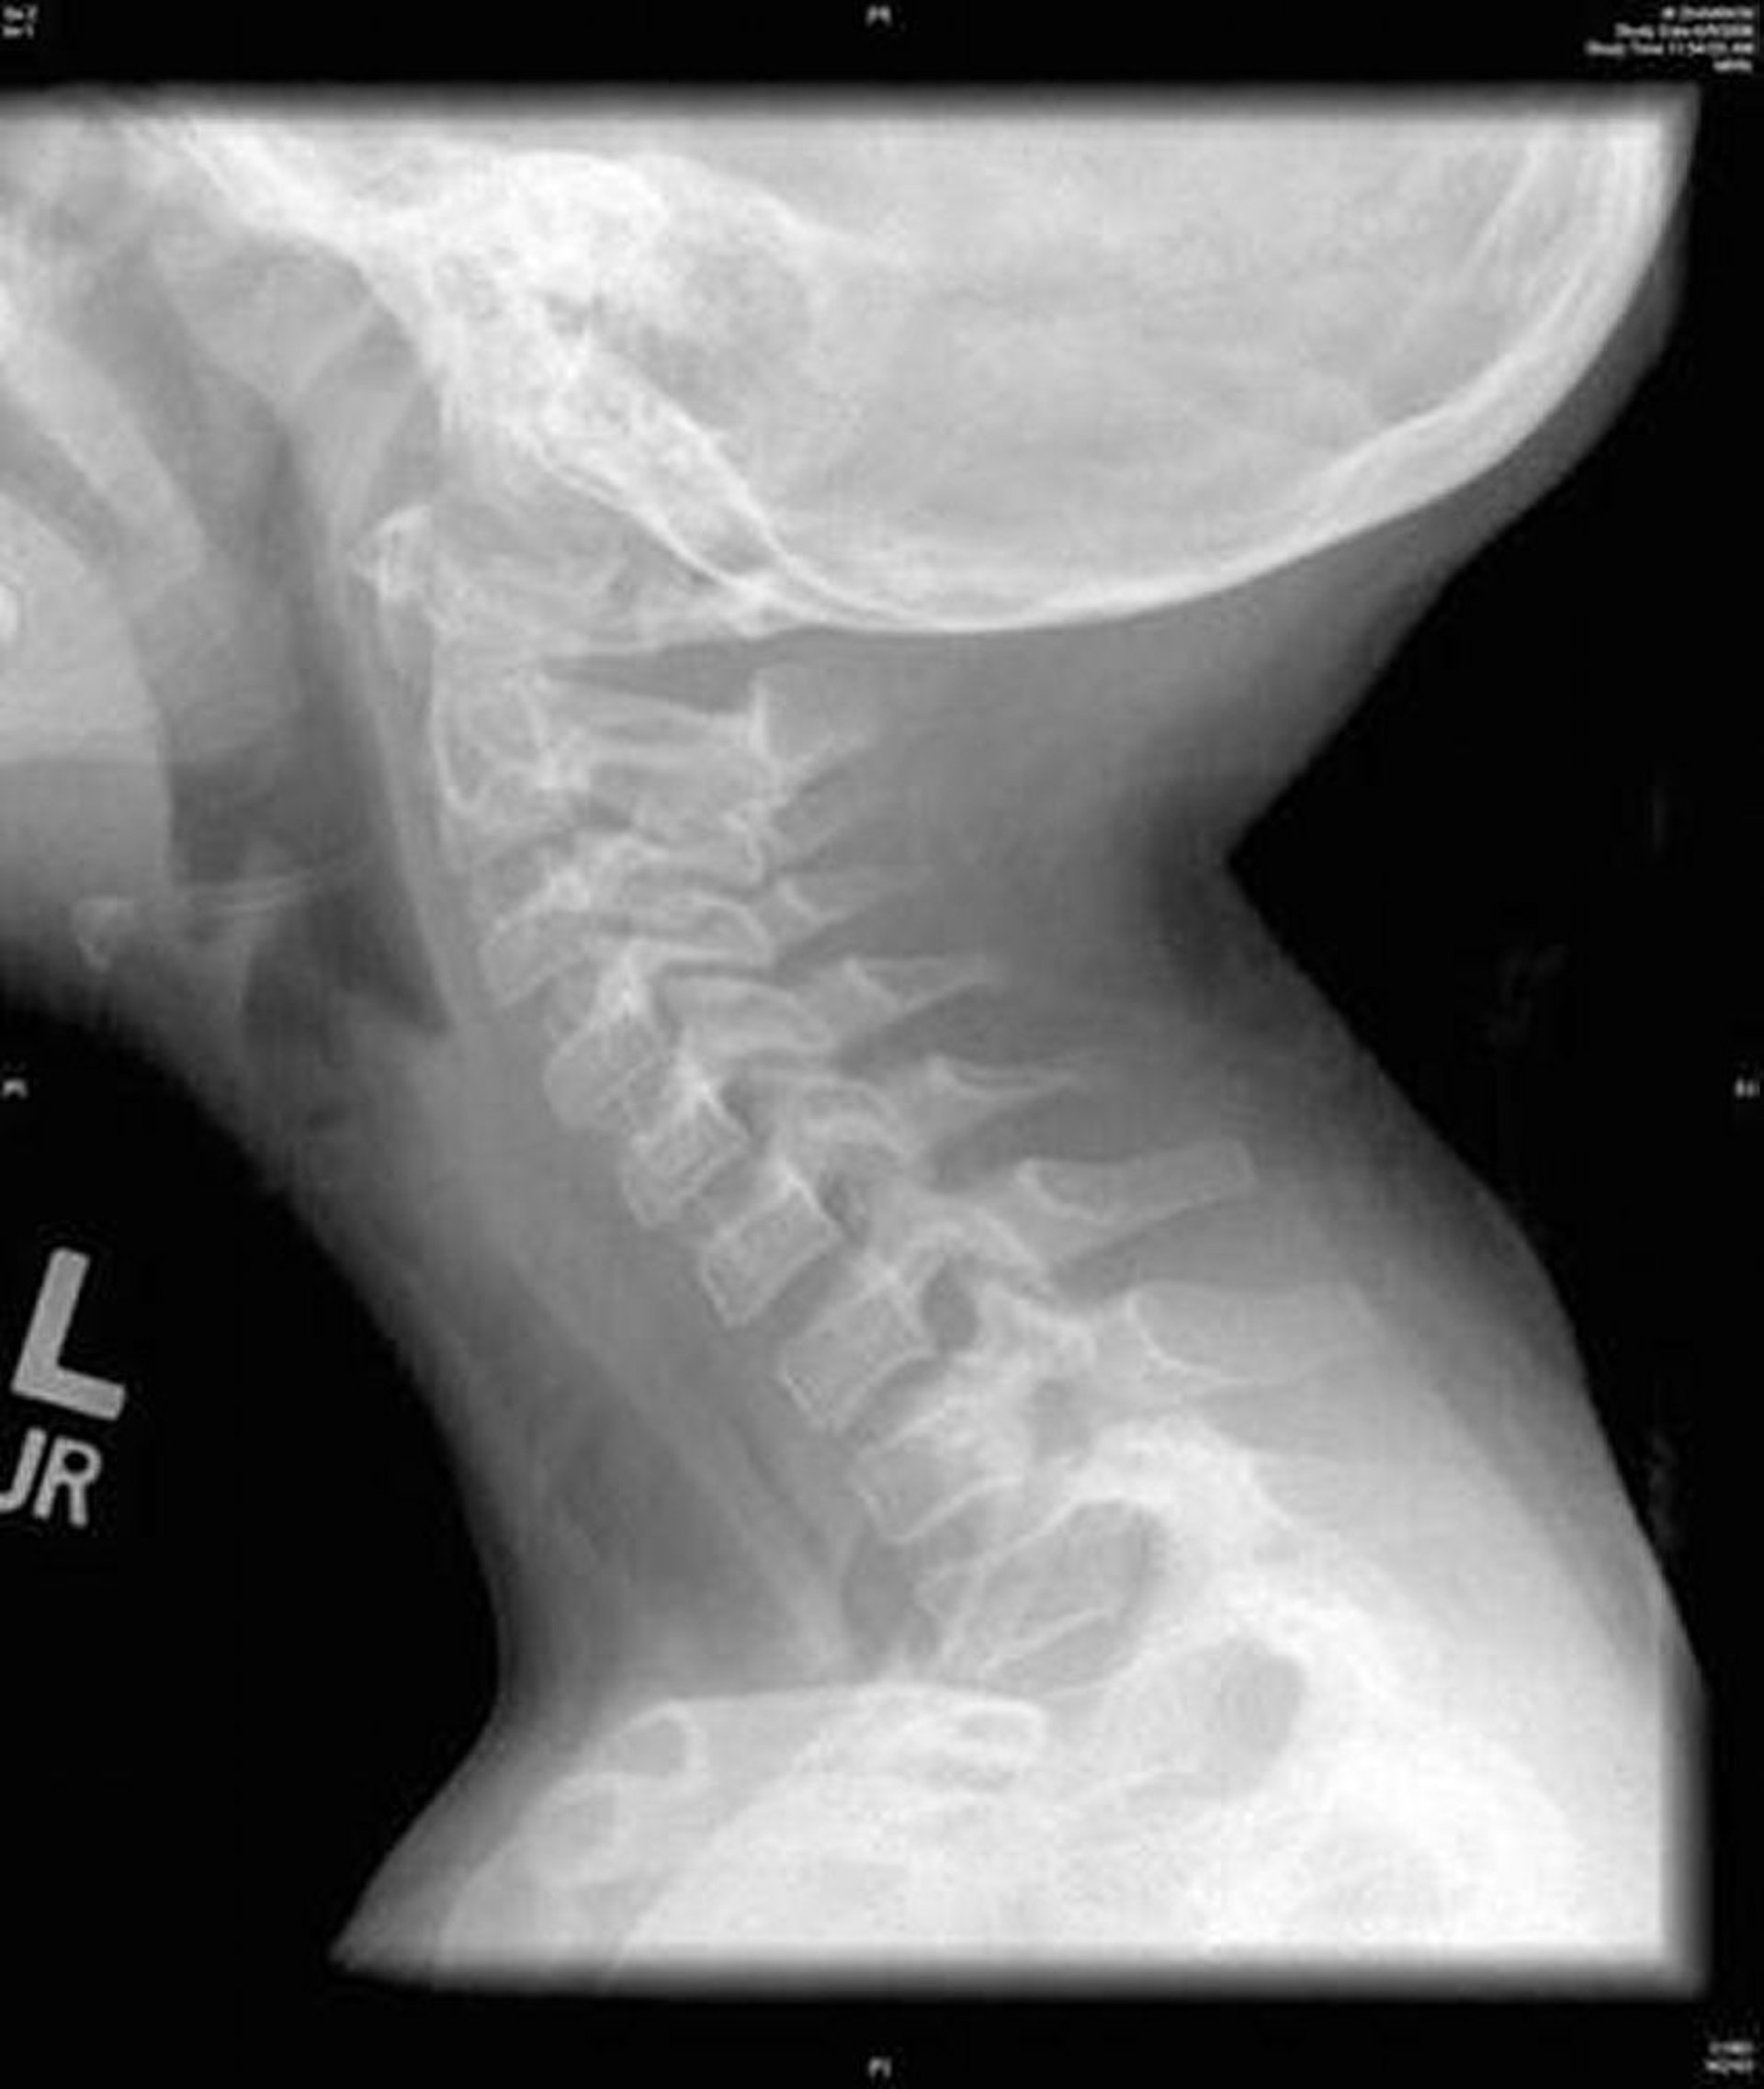

Traqueíte bacteriana (Radiografia)

Essa imagem mostra uma radiografia lateral do pescoço que revela uma irregularidade difusa da traqueia característica da traqueíte bacteriana.